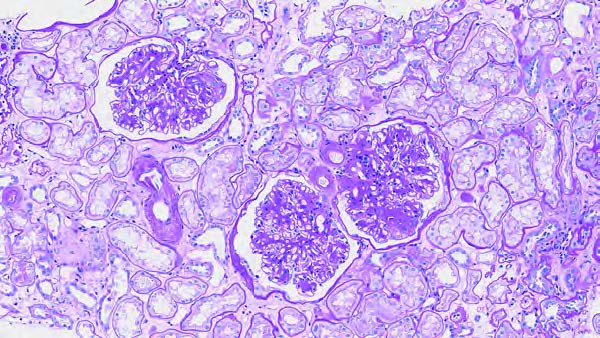

糖尿病の既往のない患者に実施した腎生検で以下の糸球体病変がみられた。鑑別診断に有用でないのはどれか。1つ選べ。

| a | タンパク尿量 |

| b | 喫煙歴 |

| c | 蛍光抗体法 |

| d | 電子顕微鏡所見 |

| e | 尿中ベンスジョーンズ蛋白 |